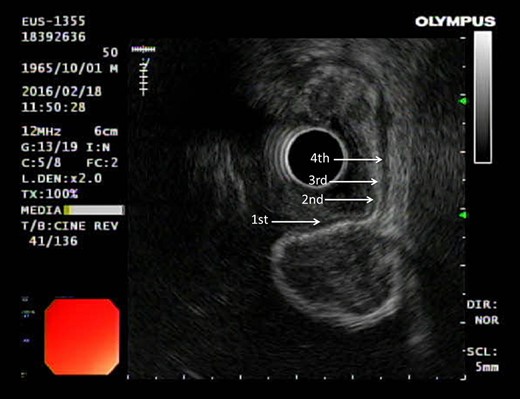

This is a 38-year-old female without any underline disease who came to our out-patient department due to a 2-month history of intermittent abdominal fullness and distension sensations. At first, she visited our gastroenterologist where medications promoting bowel motilities were prescribed but in vain. To further assess her condition, endoscopic ultrasonography was arranged which revealed a hypoechoic tumor with a diameter of 21.3 mm arising from the fourth layer of gastric wall. (Figs 1 and 2) An endoscopic biopsy was performed but reported negative findings due to failure in acquiring submucosal specimens on that biopsy. Based on epidemiology, gastrointestinal stromal tumor was suspected. Computed tomography was then arranged (Fig. 3) which revealed a submucosal tumor with heterogenous enhancement posterior wall of gastric antrum. No other lesion was found during that examination. Under such findings, she was then referred to a gastrointestinal surgeon for further surgical intervention.

Ultrasonography showing tumor arising from the fourth layer of the gastric wall.

Gastrointestinal stromal tumor (GIST) under ultrasonography also shares similar feature by arising from the fourth layer of the gastric wall.